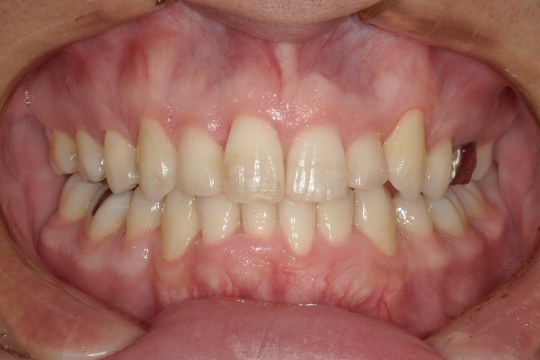

Before

浜松市中央区・自動車学校前駅のインビザラインの症例

M.I. 40代女性

上下の前歯をキレイに並べたい、中心がズレている、という主訴でご来院。上下前歯の叢生を治し、正中を合わせました。

治療の期間:R3. 4/13〜R5. 8/30

治療の価格:88万円